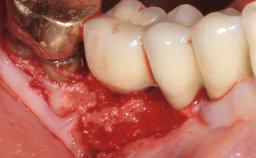

Recent clinical studies, most with short-to-medium term observation periods, have reported on the favorable clinical performance of zirconia implants in terms of survival rates, clinical, and radiographic outcomes (Roehling and coworkers 2016; Roehling and coworkers 2017; Rodriguez and coworkers 2018; Lorenz and coworkers 2019). Nonetheless, a rather high incidence of peri-implant disease at zirconia implants (39% of implants) was noted throughout a two-year period, highlighting the need for treatment protocols of peri-implant diseases at zirconia implants (Becker and coworkers 2017).